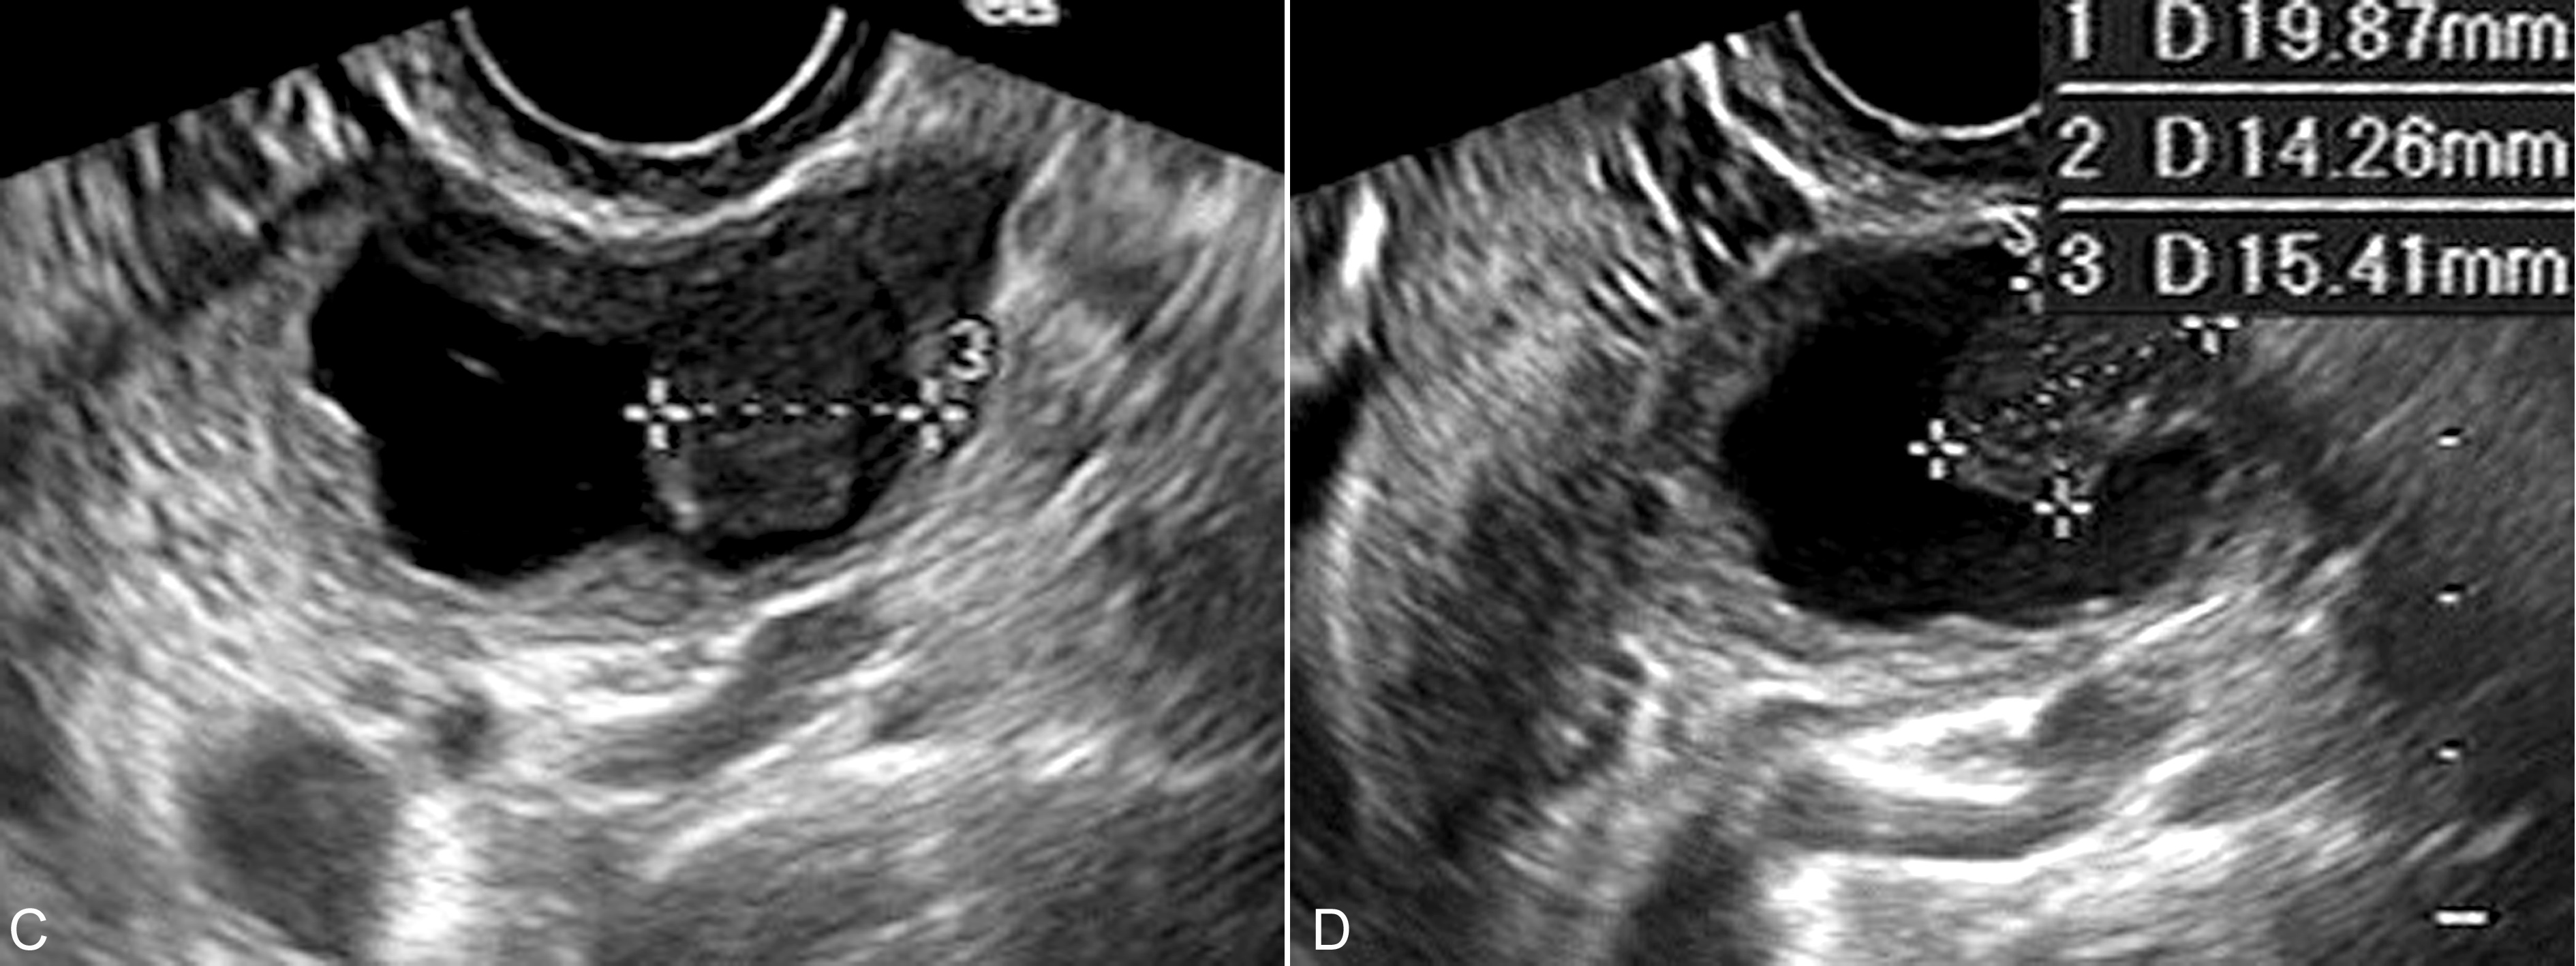

图6卵巢恶性粘液瘤声像图

C、D:瘤体内为无回声,一侧可见不规则乳头状回声,测量为20mm × 14mm × 15mm